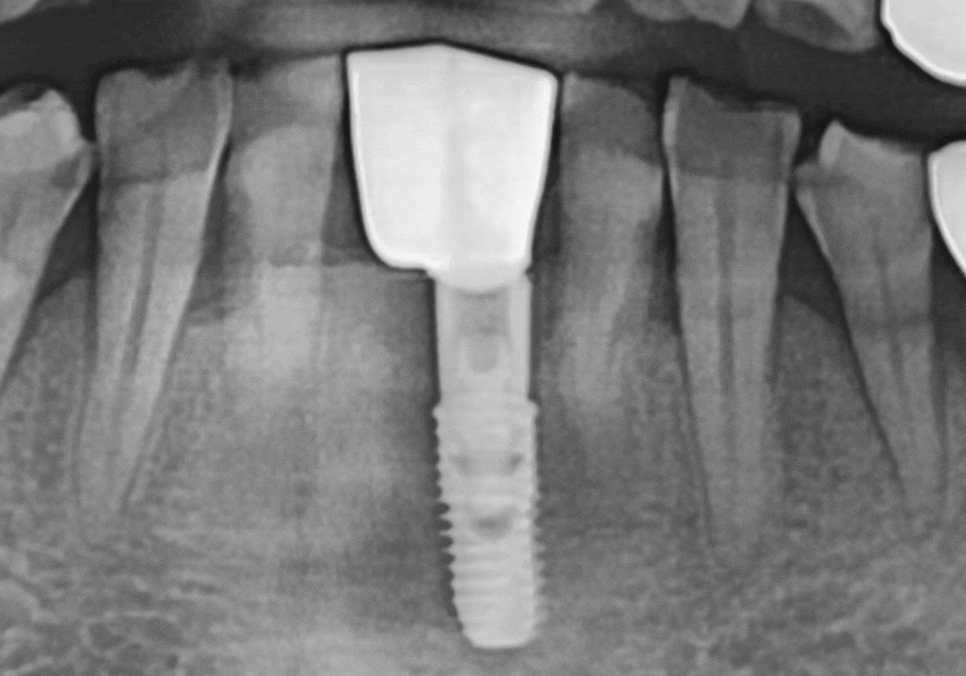

방사선 진단 결과,

치조골(뼈)이 전반적으로

많이 흡수되어 있었고,

241120

그로 인해 치아 뿌리를

지지하는 힘이 부족해

치아가 흔들리는 상태였습니다.

임플란트 1개로 2개를 버틴다면, 지지대는 더 든든해야 합니다.

강동구 임플란트 가격 줄이는 방법

다만 여기서 중요한

포인트가 있습니다.

임플란트를 1개만 심고

크라운을 2개로 연결하는 구조라면,

말 그대로 임플란트 뿌리(픽스처) 1개가

보철 2개를 지지해야 합니다.

그래서 이번 케이스는

일반적인 앞니용처럼

얇은 직경의 픽스처를 쓰기보다는,

직경이 더 큰 임플란트를 사용

가능한 범위 안에서

조금 더 직경이 넓은 픽스처로

계획해 안정성을 확보했습니다.

'개수는 줄이되, 지지대는 더 든든하게'

이런 방향으로 이해하시면 됩니다. ^^